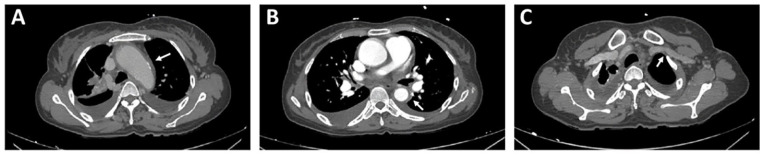

高松动脉炎(TA)是一种罕见的肉芽肿性血管炎,影响主动脉及其主要分支,而系统性红斑狼疮(SLE)是一种多系统自身免疫性疾病,已知累及血管和血清学。虽然这两种疾病具有一定的免疫病理途径,但它们的共同发生是极其罕见的。我们报告一例44岁的印度女性,先前诊断为SLE,表现为呼吸困难、心悸和结节性外膜炎。心血管检查显示颈动脉硬化、外周脉搏减少、血压差异和提示瓣膜功能障碍的杂音。实验室检查显示红细胞沉降率升高,低色性小细胞贫血,低补体血症,抗核抗体和抗dsdna抗体阳性,蛋白尿。影像学证实升降主动脉周向增厚及左颈动脉系统闭塞性病变。根据2022年ACR/EULAR分类标准,建立合并TA的诊断。治疗包括皮质类固醇和霉酚酸酯,选择环磷酰胺,因为交界性肾功能和生育考虑。尽管计划进行主动脉根置换,但患者病情恶化并死于严重的主动脉反流并发症。本病例强调了重叠自身免疫性血管炎诊断的复杂性,并强调了早期识别、严格应用分类标准和个体化免疫抑制策略的必要性,以优化此类罕见病例的预后。

Takayasu arteritis (TA) is a rare granulomatous vasculitis affecting the aorta and its major branches, while systemic lupus erythematosus (SLE) is a multisystem autoimmune disorder known for vascular and serological involvement. Although both diseases share certain immunopathological pathways, their co-occurrence is exceedingly rare. We report a case of a 44-year-old Indian female with a prior diagnosis of SLE who presented with breathlessness, palpitations, and nodular episcleritis. Cardiovascular evaluation revealed carotid bruit, diminished peripheral pulses, blood pressure discrepancies, and murmurs suggestive of valvular dysfunction. Laboratory investigations demonstrated elevated erythrocyte sedimentation rate, hypochromic microcytic anemia, hypocomplementemia, positive antinuclear and anti-dsDNA antibodies, and proteinuria. Imaging confirmed circumferential thickening of the ascending and descending aorta and occlusive disease in the left carotid system. Based on the 2022 ACR/EULAR classification criteria, a diagnosis of concomitant TA was established. Management included corticosteroids and mycophenolate mofetil, chosen over cyclophosphamide due to borderline renal function and fertility considerations. Despite planning for aortic root replacement, the patient deteriorated and succumbed to complications of severe aortic regurgitation. This case highlights the diagnostic complexities of overlapping autoimmune vasculitides and emphasizes the need for early recognition, rigorous application of classification criteria, and individualized immunosuppressive strategies to optimize outcomes in such rare presentations.